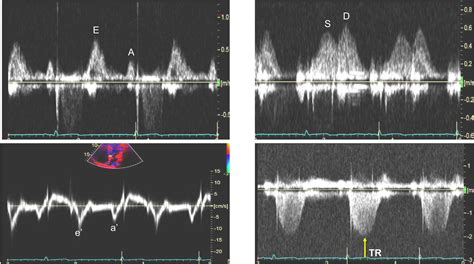

• Non-Invasive Measurement Techniques: Developing non-invasive methods for measuring PCWP could reduce the risks associated with invasive procedures and make monitoring more accessible.